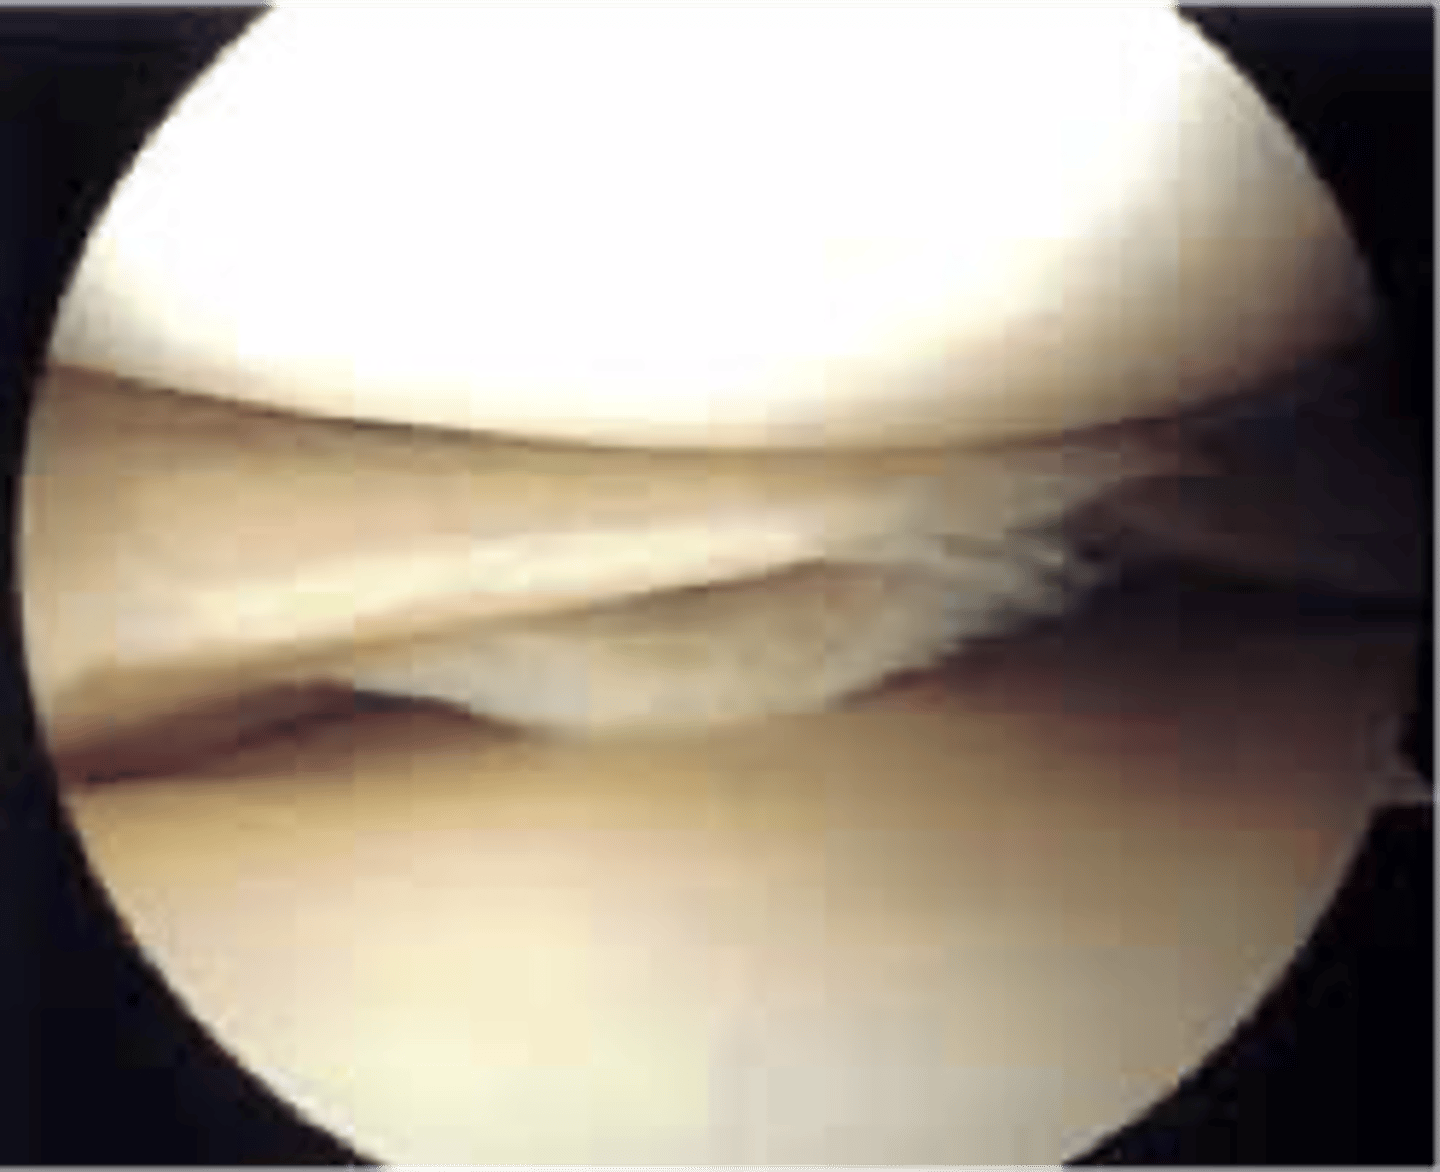

meniscus

c-shaped wedges of fibrocartilage between tibial plateau and femoral condyle

magnetic resonance imaging (MRI)

shows us bones and soft tissues (diagnostic modality of choice for soft tissue and thus the knee)

surgical treatment for meniscal tear

arthroscopic debridement or repair

How many ports enter the knee in arthroscopic surgery?

1. camera

2. irrigating instrument (lets in sterile saline)

3. trimming instrument